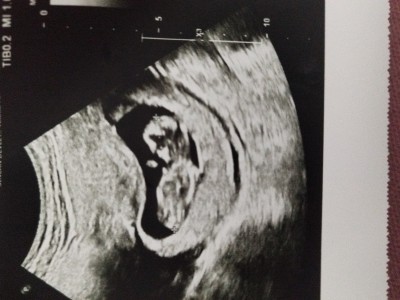

Kızlar cinsiyeti nedir acaba kese şekline göre tahmin ediyosunuz siz bende çok merak ediyorum 😄

Gebelik haftası 11+6

Erkek bebek

Keseye göre erkege benziyor

İnşallah ya iki kızım var buda hayırlısıyla inşallah erkektir teşekkür ederim